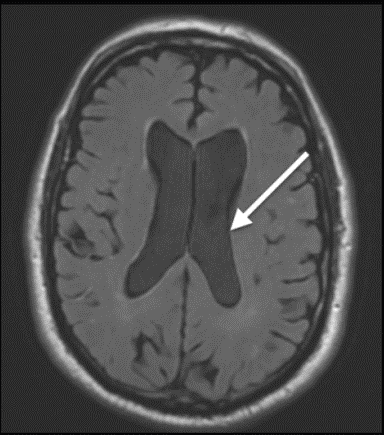

aliasing (ear lobe into middle of image)

flow artifact